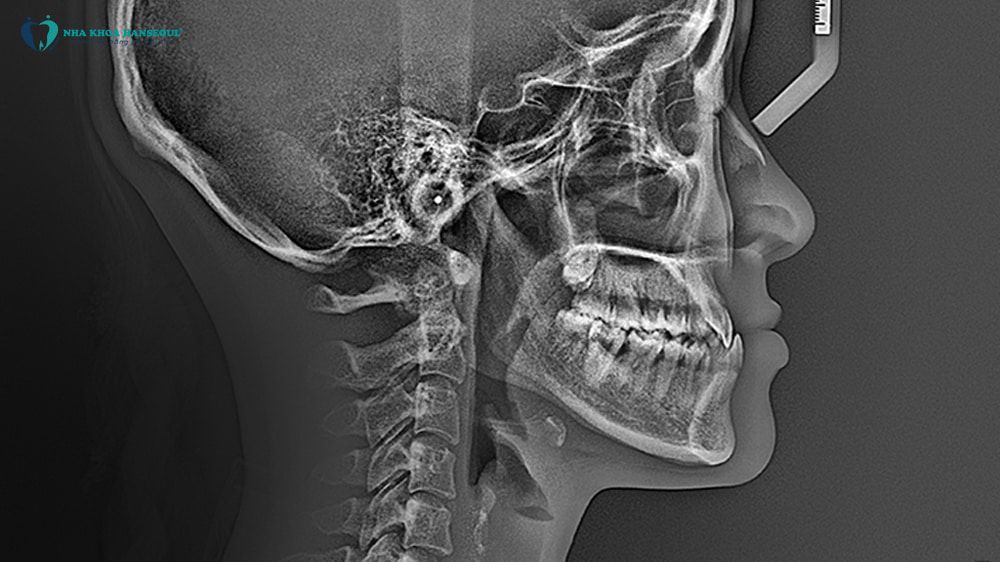

Tháng 4/2024, Duyên được bác sĩ CKII Trịnh Thị Hồng Gấm thăm khám và chẩn đoán khớp cắn ngược (khớp cắn loại III) kèm theo răng thưa. Tình trạng này không chỉ ảnh hưởng thẩm mỹ mà còn tác động đến khớp thái dương hàm, chức năng ăn nhai. Duyên quyết định bước vào hành trình chỉnh nha để lấy lại nụ cười mà mình luôn mong ước.

Bác sĩ Gấm chỉ định niềng răng mắc cài kim loại 3M Mỹ và nhổ hai răng khôn số 38 – 48 để tạo không gian cho cung răng dịch chuyển đúng sinh lý.